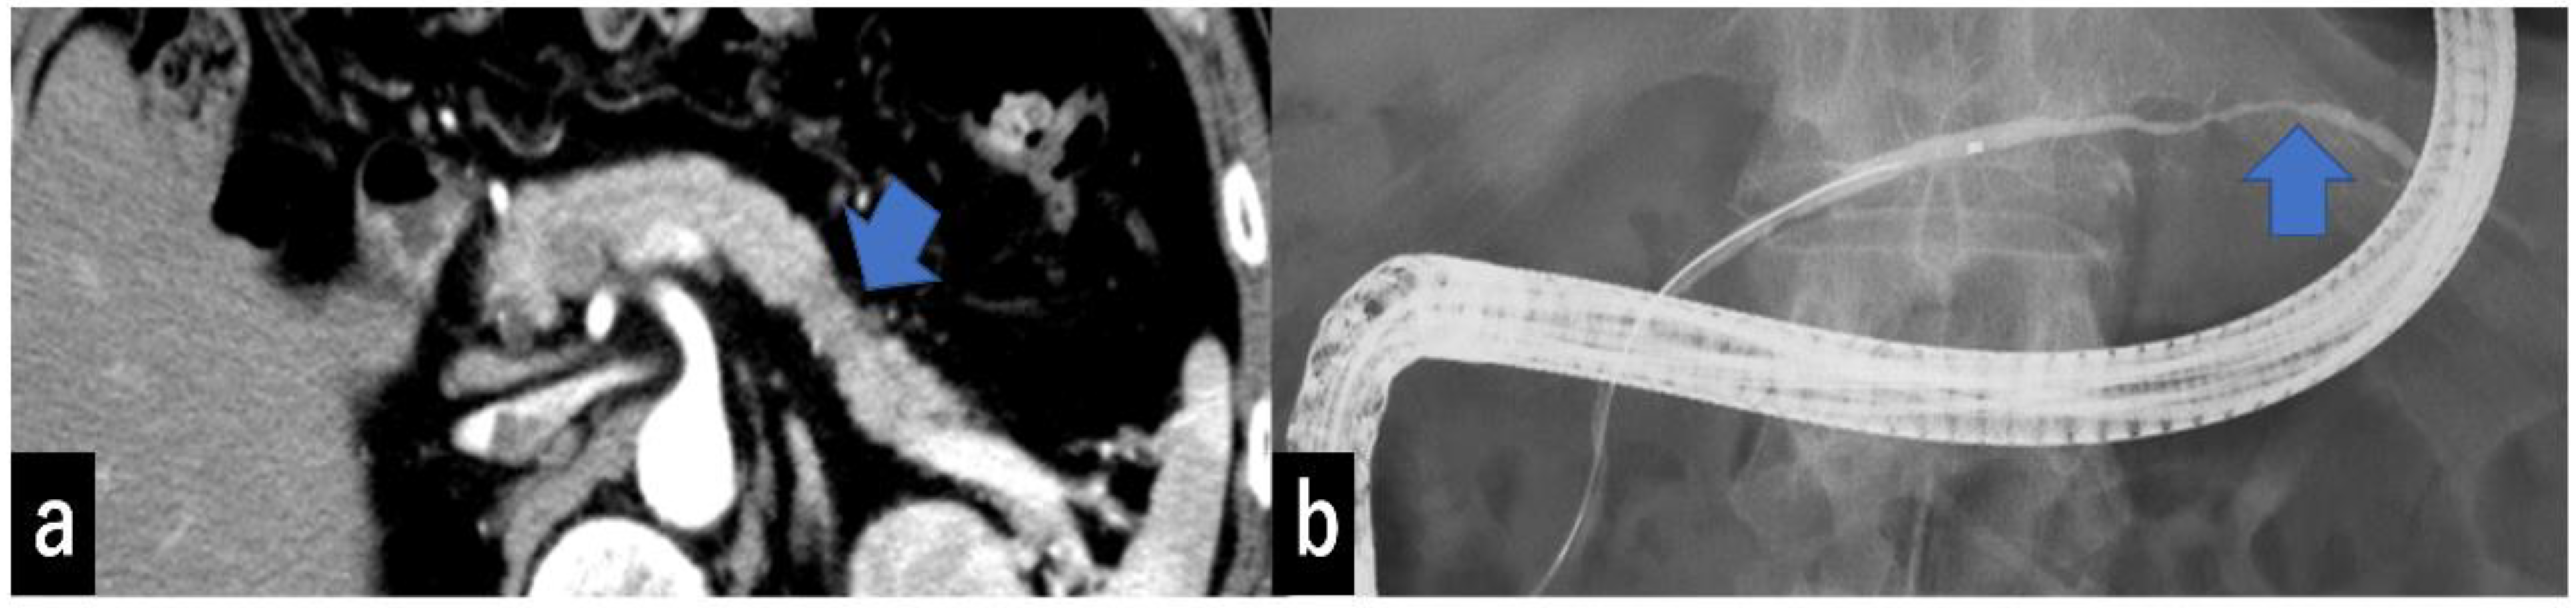

3.3. Imaging Findings